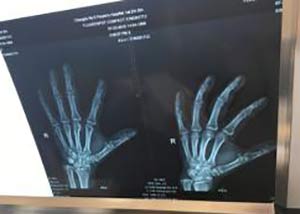

(图:患者双手、双膝有明显痛风石,手指伴有轻微变形)

体查:右手中指关节视诊肿胀明显、按压疼痛感明显,右膝关节视诊明显肿胀,按压轻微疼痛感、下蹲暂未异常,其它关节暂无任何明显异常。

实验室检查:两拇指关节轻度增生,肿胀,局部呈暗红色,有明显压痛,舌质淡,舌苔白腻,血尿酸597ummol/l,白细胞3.6×10g/L,血沉23mm/h,尿常规正常,肾功能轻度异常。